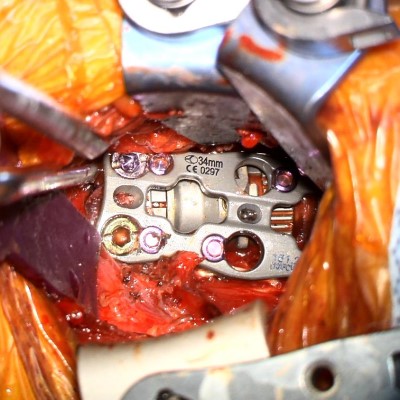

- Intra-op